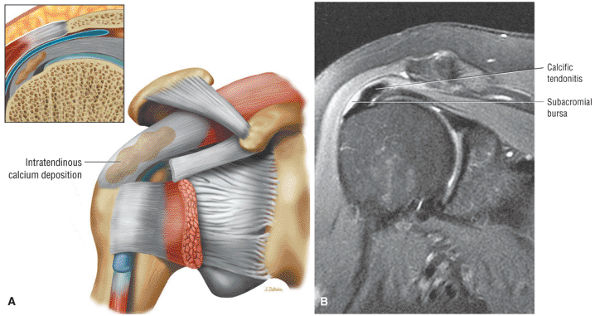

FIGURE 8.102 ● (A) The anterior undersurface of the acromion and the coracoacromial ligament form the coracoacromial arch. The subacromial subdeltoid bursa facilitates the passage of the rotator cuff and proximal humerus under the coracoacromial arch. (B) A superior axial image shows the anterior-to-posterior extent of the coracoacromial (CA) ligament perpendicular to the supraspinatus tendon. The fluid in the subacromial-subdeltoid bursa represents fluid between two serosal surfaces in contact with each other. One serosal surface is contributed by the undersurface of the coracoacromial arch and deltoid, and the other serosal surface is on the bursal side of the cuff.

|

![]() |

FIGURE 8.103 ● Pseudospur. The normal broad attachment of the coracoacromial ligament to the inferior surface of the acromion is shown on (A) T1-weighted coronal oblique and (B) sagittal oblique images. The low-signal-intensity acromial cortex (black arrows) and adjacent coracoacromial ligament and lateral slip of the deltoid attachment (white arrows) give the false impression of a small subacromial spur in the coronal plane. This pseudospur should not be misinterpreted as impingement; otherwise, unnecessary acromioplasties may be performed on patients with a normal coracoacromial ligament attachment and no associated acromial spurs.

-